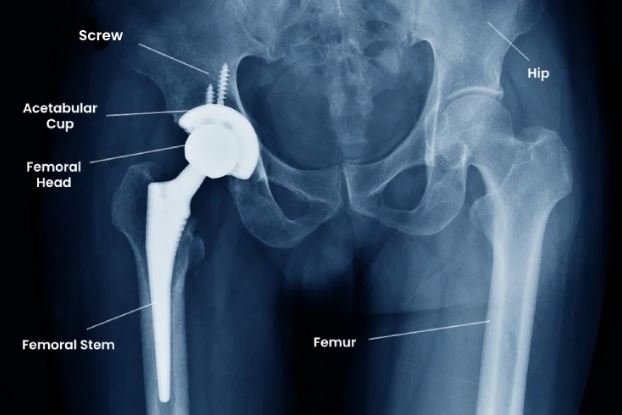

Total hip replacement involves removing the damaged femoral head and acetabular surface and replacing them with artificial components made of metal, ceramic, or polyethylene materials.

Patients often report improved sleep and independence within weeks of surgery. Modern implants can last 15–25 years or more, depending on patient factors.